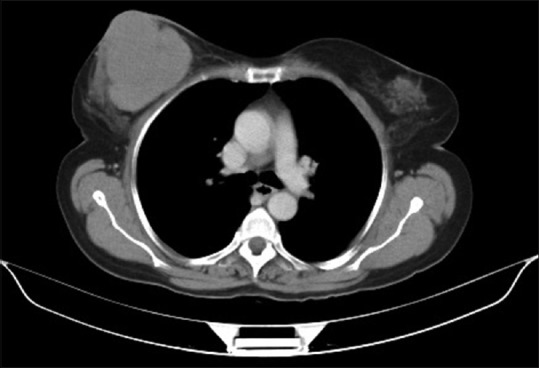

A 65-year-old female with no history of comorbidities was admitted to our hospital on July 5, 2014 with painless lump in her right breast. On detailed history taking, patient had no history of fever, night sweats, or weight loss (B symptoms). Physical examination revealed a hard, nontender, mobile mass of approximately 6 cm × 7 cm occupying all quadrants of the right breast. The contralateral breast was normal. On physical examination, patient had no evidence of cervical, axillary or inguinal lymphadenopathy. Liver and spleen were not palpable. The laboratory tests revealed the following: Hemoglobin of 11.9 g/dl, total leukocyte counts of 10,400/mm3, platelet counts of 48,600/mm3, serum creatinine of 0.72 mg/dl, alkaline phosphatase of 55 IU/L, serum glutamic pyruvic transaminase of 22 IU/L, serum glutamic oxaloacetic transaminase of 13 IU/L, total bilirubin levels of 0.88 mg/dl, serum albumin of 4.34 g/dl, lactate dehydrogenase (LDH) of 172 U/L, and serum uric acid of 4.52 mg/dl. Excisional biopsy performed showed atypical lymphocytic infiltration suspicious of non-Hodgkin's lymphoma (NHL) [Figure 1]. Immunohistochemistry revealed positivity to CD20 [Figure 2], CD79a and MUM1 and negativity to CD2, CD3, CD5, CD10, and AE1. MIB-1 index was 95%. On the basis of histopathologic features, tumor was classified as DLBCL, non-germinal centre B-cell-like (non-GCB DLBCL). Bone marrow aspiration and biopsy were performed and revealed a hypercellular bone marrow with no evidence of lymphomatous infiltration. The cerebrospinal fluid cytological examination was negative for any malignant cells. Computed tomography (CT) of the neck, thorax, abdomen, and pelvis revealed 66 mm × 68 mm × 84 mm large multi-lobulated soft tissue density lesion involving all quadrants of right breast reaching up to the skin [Figure 3]. No systemic lymphadenopathy was detected. The CT findings indicated stage I E of the lymphoma tumor according to the Ann Arbor staging system. The patient received six courses of cyclophosphamide, doxorubicin, vincristine, prednisolone plus rituximab (R-CHOP) chemotherapy. After four courses of R-CHOP, the follow-up chest CT scan showed decreased the size of the right breast mass (6.6 cm × 6.8 cm → 3.4 cm × 1.4 cm) [Figure 4]. After six courses of R-CHOP, the follow-up chest CT scan showed no visible mass in the breast. The patient was put under close observation. At present, after follow-up period of 20 months, the patient is surviving with no evidence of disease and with no morbidities associated with chemotherapy.

| Figure 3:Computed tomography scan showing a large multi-lobulated soft tissue density lesion involving all quadrants of right breast reaching up to the skin measuring 66 mm × 68 mm × 84 mm